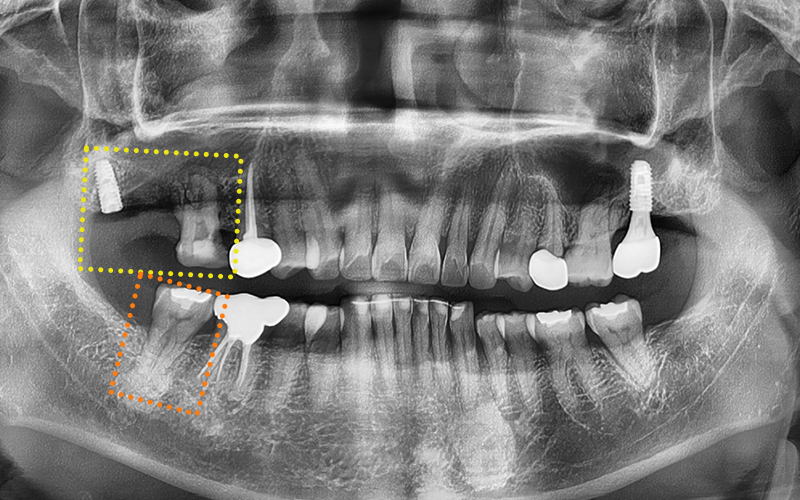

✅ Problems seen on X-ray

We then took X-ray and CT images

to precisely check the condition inside the mouth.

After looking at the X-ray, the patient also said,

"Even I can see it seems to be placed too far back."

After confirmation, maxillary sinus lift surgery

had been attempted twice but failed,

and in the end, the implant had been placed in a position

far back, similar to the location of a wisdom tooth.

Although the implant itself had successfully osseointegrated,

because the position was unclear,

it was a very unfavorable situation for fabricating the prosthetic restoration...!

In addition, the tooth in the front that was undergoing root canal treatment

had a poor prognosis and needed extraction.